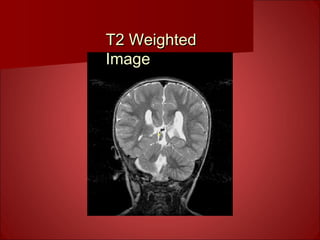

T2* and T2 ContrastT2* and T2 Contrast

• Technique: use long TR and intermediate to

long TE in SE & FSE

• Use an itermediate TE & TR for GRE with a

narrow flip angle ( 15-30)

• In F-GRE, use a very short TE & TR & very

narrow flip angle.

• Useful for functional (T2* contrast) and

anatomical (T2 contrast to enhance fluid contrast)

studies

• 1mm resolution for anatomical scans or 4 mm

resolution [better is possible with better gradient

system, and a little longer time per volume]

T2 WeightedT2 Weighted

ImageImage